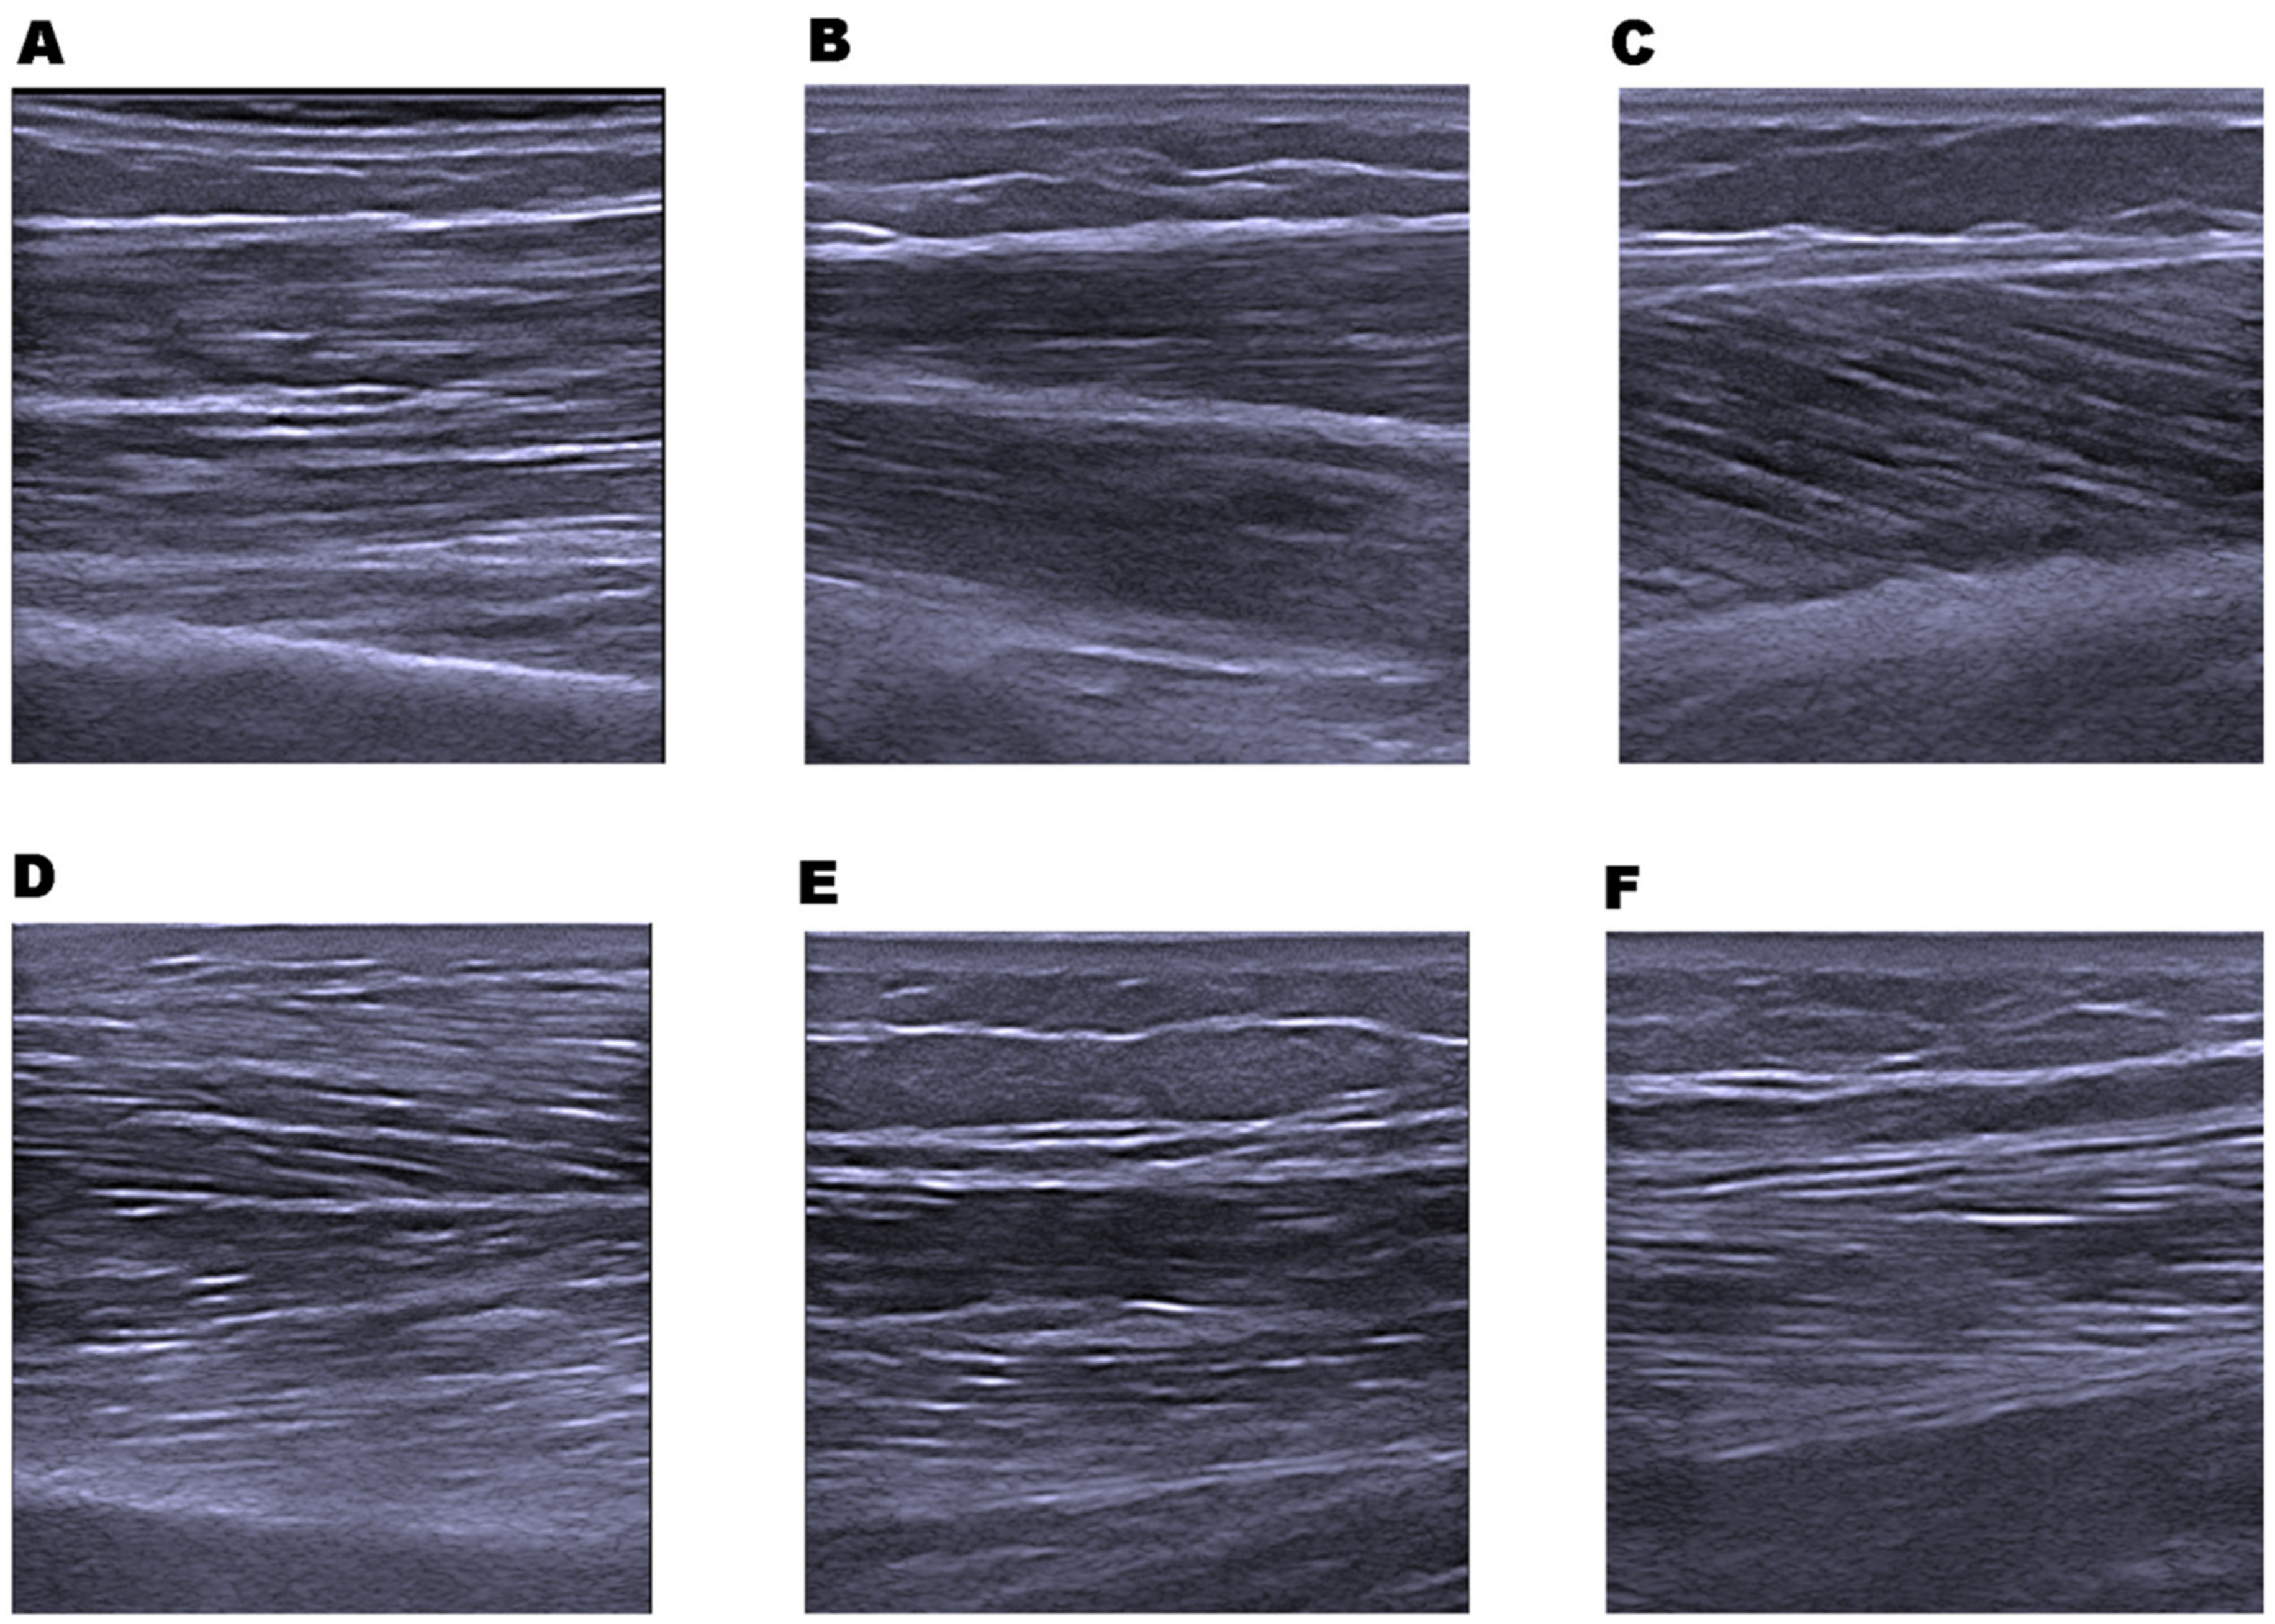

The following upper and lower limb muscles (see Figure 1) of the dominant side were examined using ultrasound B-mode images: superficial wrist flexors muscles (WF), biceps brachii (BB), rectus femoris (RF), vastus lateralis (VL), medial gastrocnemius (MG), and tibialis anterior (TA). These muscles were examined with the participant in the supine position, with the ultrasound operator standing on the ipsilateral side of the participant. MG was examined with the participant in the prone position.

Figure 1.

Example of muscle ultrasound images. (A) Biceps brachii; (B) wrist flexors; (C) medial gastrocnemius; (D) tibialis anterior; (E) rectus femoris; and (F) rectus lateralis.

Representation of superficial and deep aponeuroses was optimized in order to achieve the best muscle image possible. The transducer was placed at the anatomical location corresponding to the largest diameter of the muscles examined described in a previous study [11,12]: BB was measured at two-thirds of the distance from the acromion to the antecubital crease; WF at two-fifths of the distance from the antecubital crease to the distal end of the radius; RF half-way along the line from the anterior-superior iliac spine to the superior border of the patella; VL half-way along the line from the anterior-superior iliac spine to the superolateral border of the patella; MG from the mid-sagittal line of the muscle, midway between the proximal and distal tendon insertions and TA at one-quarter of the distance from the inferior aspect of the patella to the lateral malleolus.